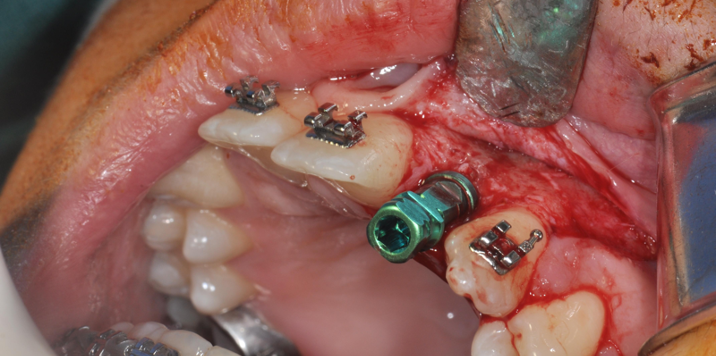

→ Pose du ou des implants

Durant cette étape, le praticien pose les implants dentaires pour remplacer les racines manquantes. À l’issue de cette intervention, vous sentirez des implants couverts par la gencive, et qu’ils sont mis en “nourrice” : cela permet à l’os de cicatriser autour des implants.

L’implant dentaire est placé dans la mâchoire sous anesthésie locale dans la majorité des cas, parfois sous anesthésie générale.

- La chirurgie implantaire guidée

La chirurgie implantaire

Vidéo de la chirurgie implantaire